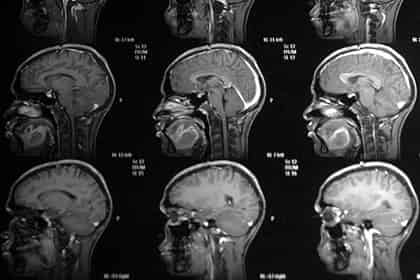

Ученые Массачусетского технологического института (МТИ) разработали новый способ доставки химиотерапевтических препаратов в глиобластому, который позволяет успешно преодолеть гематоэнцефалический барьер. Исследователи использовали липосомы, снабженные трансферинновыми «хвостами», которые попадают в злокачественные ткани, выпускают лекарство и убивают больше клеток, чем существующие методы лечения.

Гематоэнцефалический барьер (ГЭБ) препятствует проникновению микроорганизмов, токсинов и других чужеродных агентов из кровеносной системы головного мозга в нервные ткани. Это осложняет доставку лекарств, осуществляемую с помощью наночастиц, для борьбы с опухолями головного мозга.